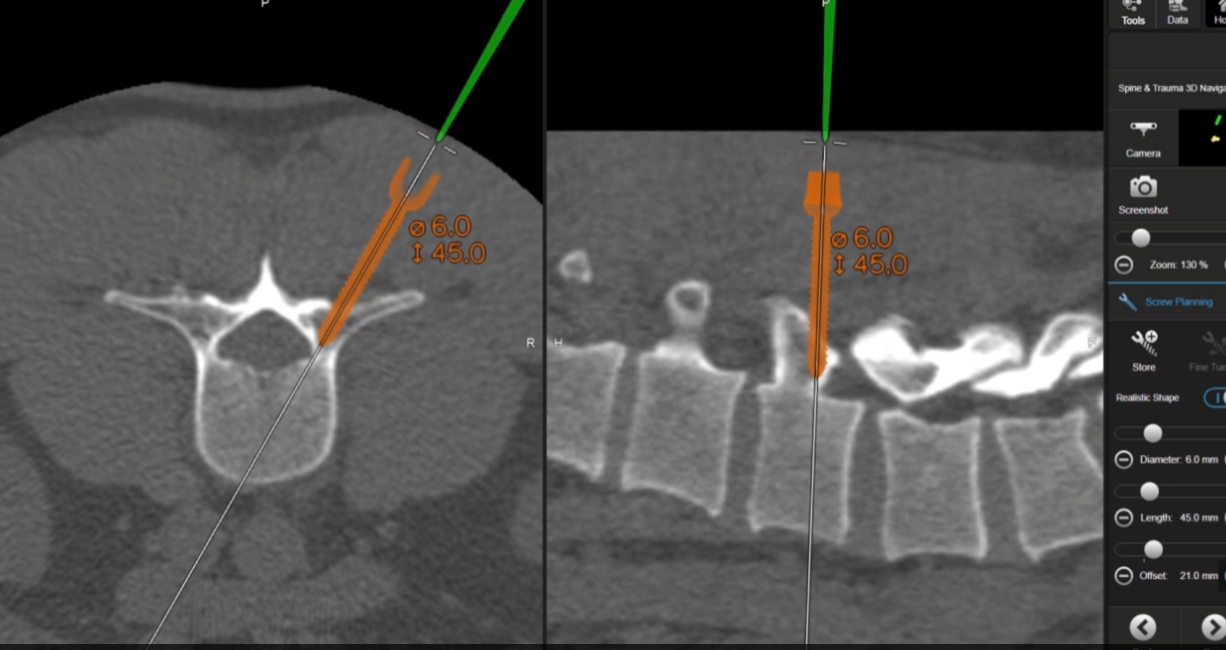

The BrainLab Spinal Navigation system allows you to navigate implants and instruments for more accurate implant placement.